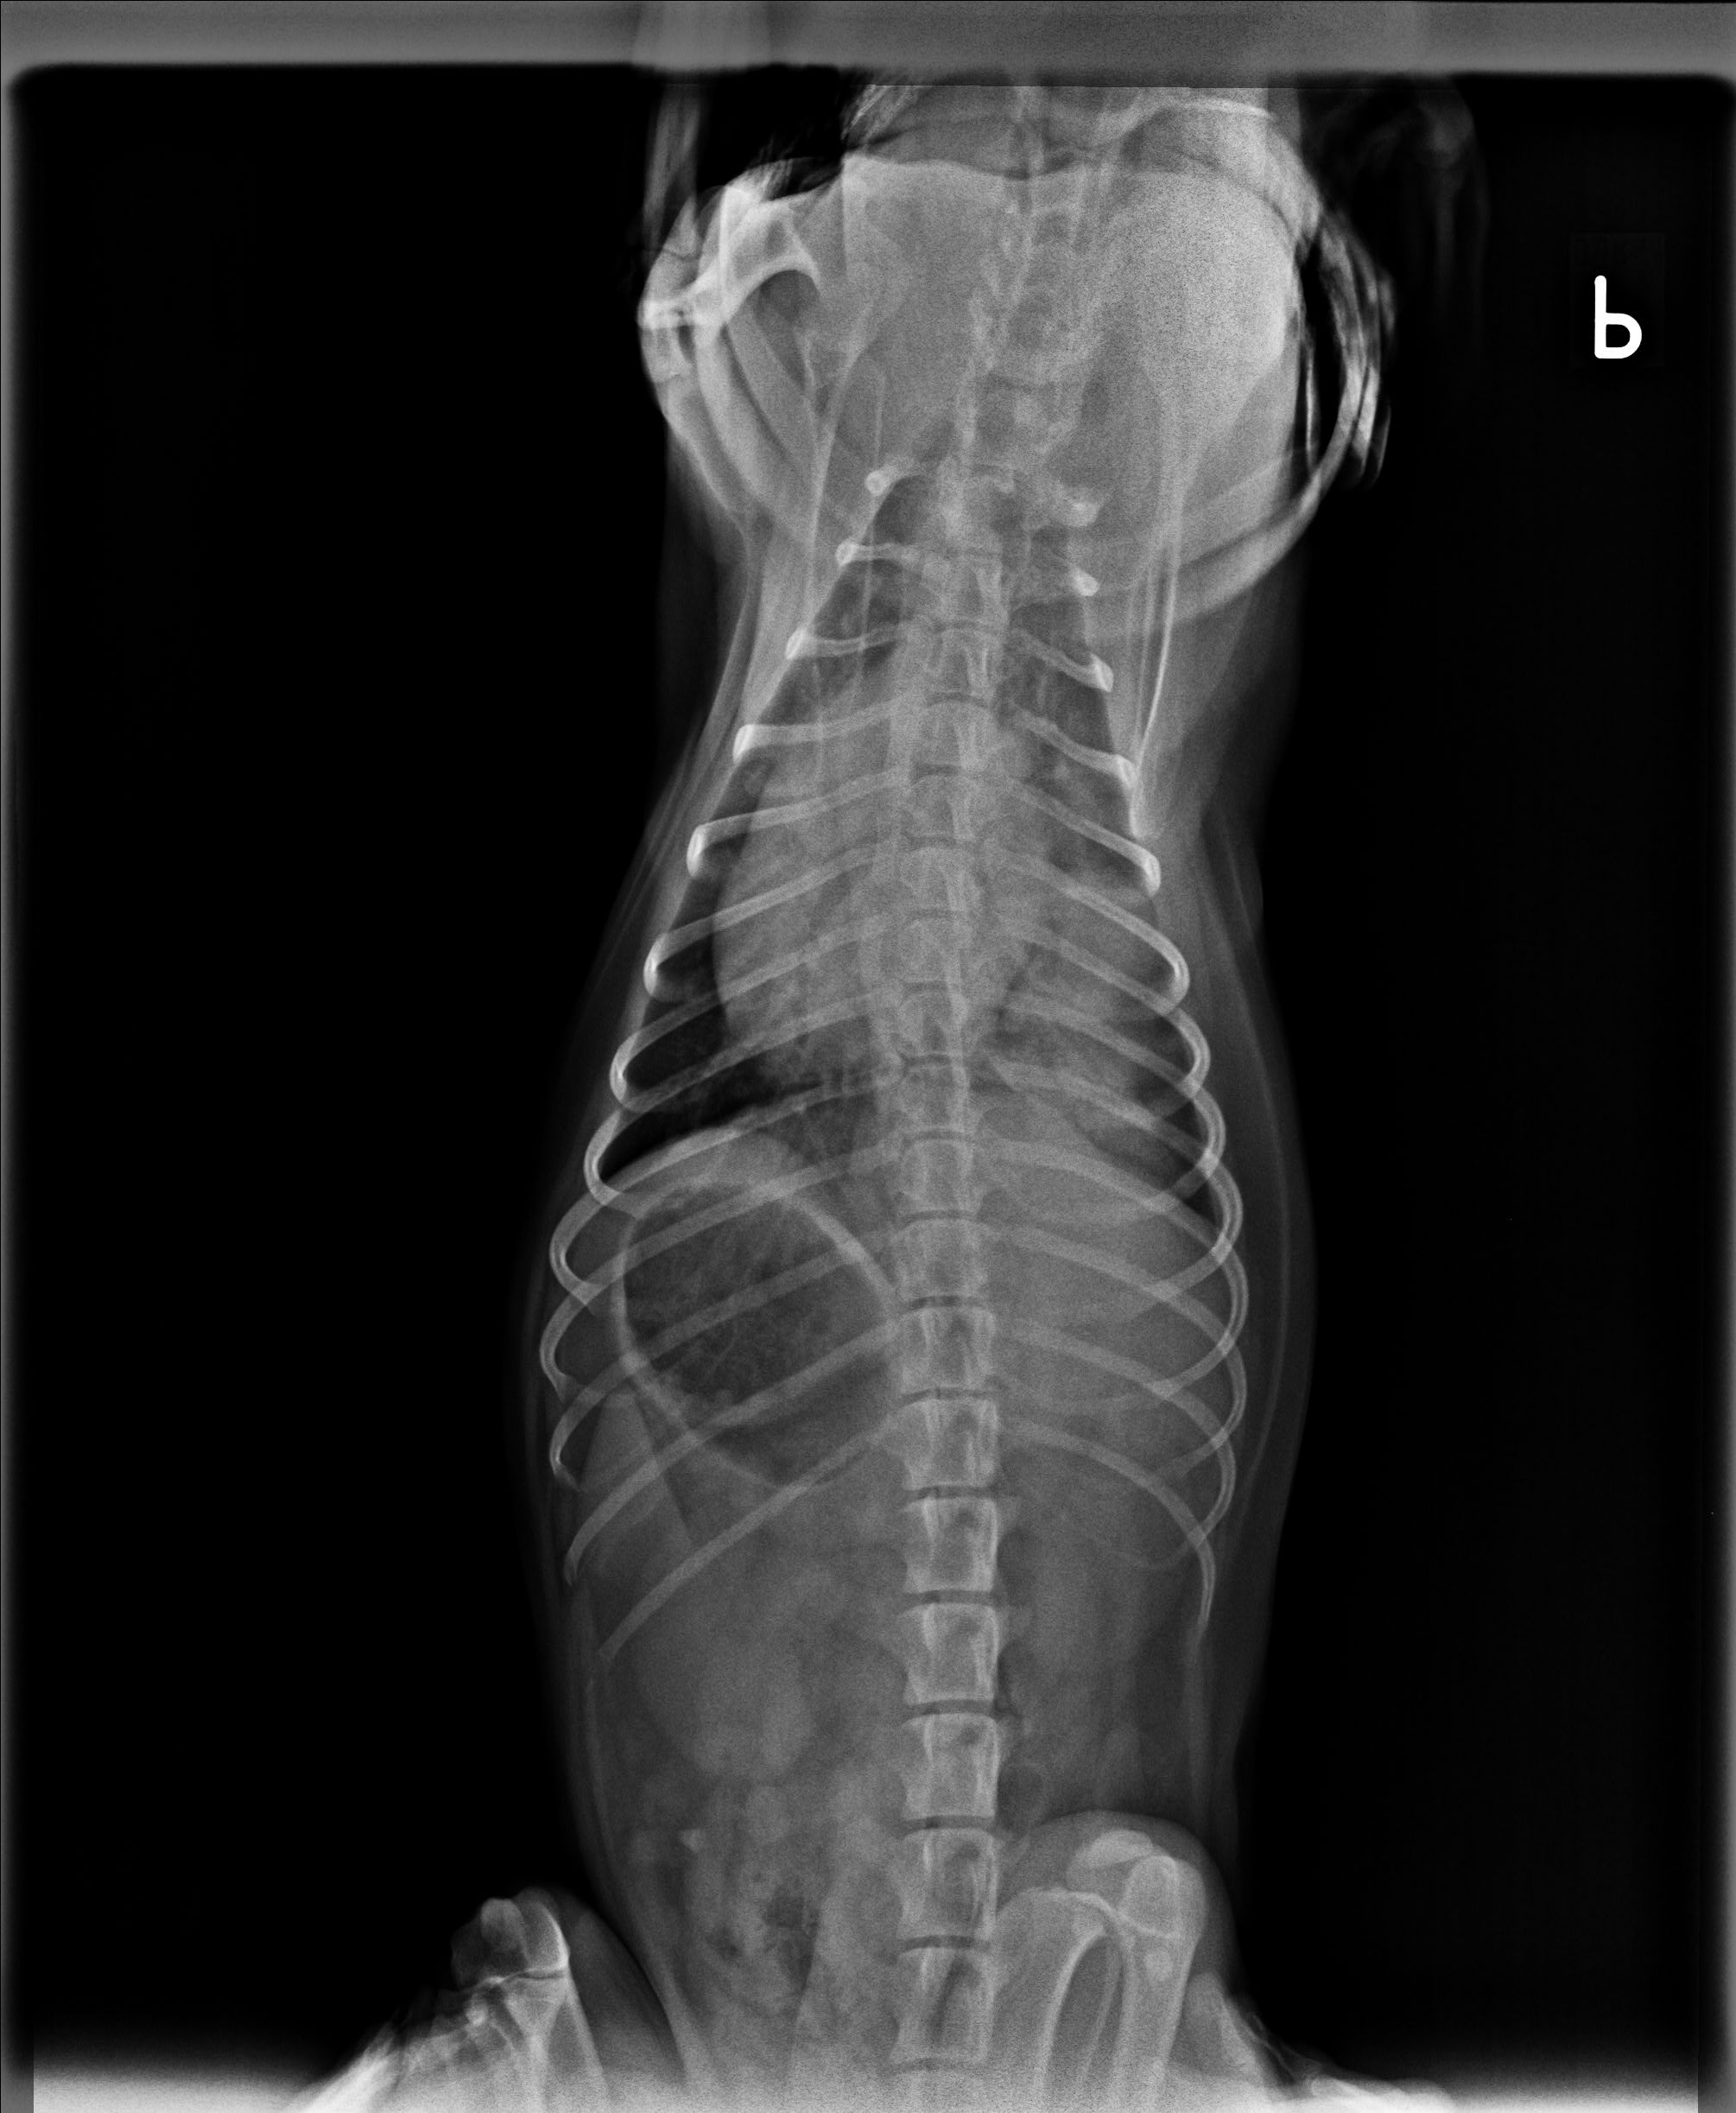

Mnoho lidí se neuvědomuje, že rakovina se týká nejen člověka, ale také našich domácích mazlíčků. Rakovina patří mezi nejčastější zabijáky psů i koček. Zde je několik příznaků, které vám napoví, že s vaším mazlíkem není něco v pořádku. Nutně to nemusí znamenat to nejhorší, je ale potřeba co nejrychleji vyhledat veterináře. Stejně jako u lidí platí – čím dříve se na nemoc přijde, tím lépe.